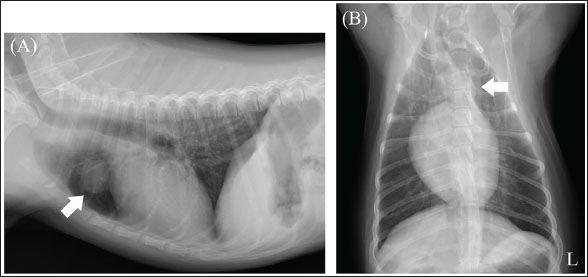

A neutered 9-year-old male Papillon weighing 3.5 kg was referred to the Okayama University of Science Veterinary Medical Teaching Hospital for examination and treatment of an incidentally discovered mass in the cranial intrathoracic cavity during regular medical checkups. The dog had no clinical signs and was in good general condition. However, a mass in the cranial thoracic region was detected by chest radiography. Blood tests showed no hypercalcemia, and arterial blood gas analysis showed no problems (Table 1). Polycythemia, slight hypernatremia, and hyperchloremia, which may be related to dehydration, were also observed. A chest X-ray revealed a mass of approximately 20 mm in the cranial intrathoracic cavity and mild expansion of the mediastinum (Fig. 1). The tumor-associated syndromes, such as megaesophagus and myasthenia gravis, were not observed. Computed tomography (CT) was performed under general anesthesia (Aquilion Lightning; Canon Medical Systems Co., Tokyo, Japan). Iopamidol (Oypalomin 300, Fuji Pharma, Japan) was used as a contrast medium (injection volume, 2.5 ml/kg [750 mgI/kg]; injection time, 15 seconds). Precontrast, arterial phase, venous phase, and equilibrium phase scans were obtained. The cranial intrathoracic mass (length, width, and height of 18.3, 16.0, and 18.6 mm, respectively) was a solitary lesion within the cranial mediastinum (Fig. 2). The mass was well demarcated, and there was no evidence of invasion into the surrounding blood vessels. The CT values of the mass were 43.2, 50.6, 113.1, and 102.2 HU for the precontrast, arterial, venous, and equilibrium phases, respectively (Fig. 2). These contrast enhancement effects were a preliminary diagnosis that the mass was a thymoma (Von Stade et al., 2019). Enlarged surrounding lymph nodes or distant metastasis were not detected. Due to the small size of the mass and its absence from the thoracic cavity margin, preoperative pathological examination could not be performed. Based on the CT results, the mass was provisionally diagnosed as a thymoma. The thymoma volume was measured from the length, width, and height by computed tomography using the elliptical volume formula. The cranial intrathoracic volume was measured using a 3D image analysis software (Ahmics-VAZE, PetCommunications Co., Ltd., Osaka, Japan). The cranial intrathoracic region between the first and fourth sternum at the beginning of the cranial intrathoracic cavity was assumed to be the surgical space for VATS-T (Fig. 3). The dorsal cephalic end was designated as the point where the first sternum extends perpendicularly and joins the thoracic vertebrae, and the dorsal caudal end was designated as the point where the fourth sternum extends perpendicularly and joins the thoracic vertebrae. This region was extracted and its volume was measured using the 3D volume rendering function by Ahmics-VAZE. The ratio of thymoma volume to cranial intrathoracic volume (T/CI ratio) was calculated as follows: thymoma volume/cranial intrathoracic volume × 100). The thymoma volume was 2.3 cm3, the cranial intrathoracic volume was 97.7 cm3, and the T/CI ratio was 2.4%. The thymoma volume was calculated using the approach in a previous report of two cases that described the thoracoscopic resection of thymomas (Mayhew and Friedberg, 2008). We also calculated the cranial intrathoracic volume for the dog, as it was of the same breed and weight as the two reported cases. Subsequently, we calculated the T/CI ratio. In previous reports, the thymoma volumes were 9.5 cm3 and 36.6 cm3, respectively, and the cranial intrathoracic volume was 892.8 cm3. The T/CI ratios were 1.1% and 4.1%, respectively.

Fig. 1. Chest X-ray imaging. (A) Right lateral view. (B) Ventrodorsal view. X-ray image: a tumor-like lesion measuring approximately 20 mm was observed on the cranial side of the heart (white arrow) (L): Left side.